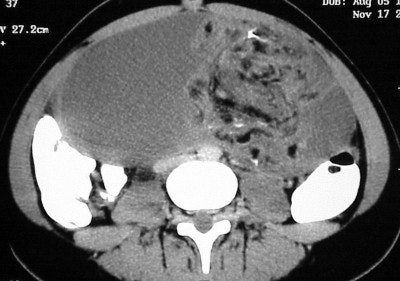

Axial images (Figures CT 10 and CT 11) show a mass beginning just below the kidneys on the left side and extending almost through the pelvis. The child was diagnosed with Wilm’s tumor of the left kidney.

![]() |

| Figure CT 11 |

She underwent a left nephrectomy and chemotherapy and recovered well.